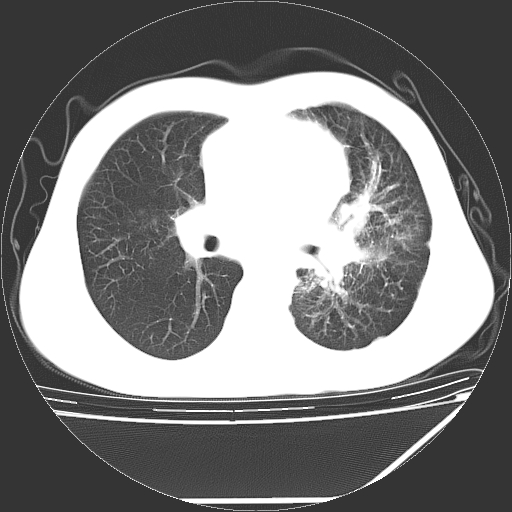

男,13岁,咳嗽、咳痰伴发热一周。

中上纵隔见多枚淋巴结肿大,部分相互融合成团片,左肺门增大,上叶支气管变窄,肺内多处斑片状 索条状及棉絮状致密影。临床“男,13岁,咳嗽、咳痰伴发热一周。”首先考虑:原发综合征!不除外淋巴瘤可能!

纵隔多发肿大淋巴结,部份有融合改变。双肺血管气管束增厚,以肺门为中心向外周散发,以左肺下叶为明显。考虑淋巴瘤可能性大。不除外原发综合征。

中上纵隔见多枚淋巴结肿大,部分相互融合成团片,左肺门增大,上叶支气管变窄,左肺支气管血管束增粗,可见磨玻璃样影。临床“男,13岁,咳嗽、咳痰伴发热一周。”首先考虑:淋巴瘤可能性大!

左肺野见淡片状影,病因整体多考虑结核

单纯看片子感觉左侧肺通气不畅,而不像肺内病变引起的纵隔病变。而且纵隔及左肺门都有淋巴结增大。首先还是考虑一下结节病,不排除淋巴瘤!!!